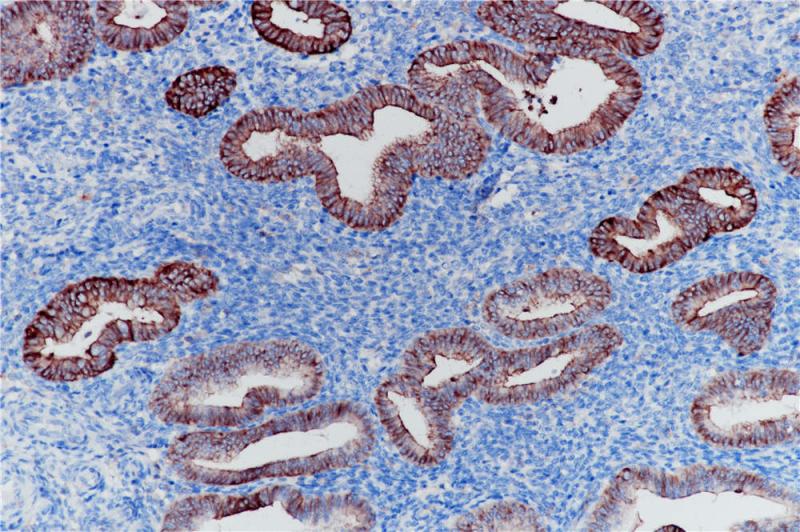

MHC II(DRα chain) 重组兔单克隆抗体

主要组织相容性复合体 II 类(MHC II 类)分子是在巨噬细胞、树突细胞和 B 细胞等抗原呈递细胞表面表达的异二聚体的跨膜糖蛋白。在人体中,MHC II 类蛋白复合体被人白细胞抗原基因复合体 (HLA) 编码。MHC II可在 B 淋巴细胞、活化的 T 淋巴细胞、活化的自然杀伤 (NK) 细胞等表达。

阳性对照

食管